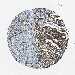

LIVER CANCER - Protein expressioni

A mouse-over function shows sample information and annotation data. Click on an image to view it in a full screen mode. Samples can be filtered based on level of antibody staining by selecting one or several of the following categories: high, medium, low and not detected. The assay and annotation is described here.

Note that samples used for immunohistochemistry by the Human Protein Atlas do not correspond to samples in the TCGA dataset.

Antibody stainingi

Antibody staining in the annotated cell types in the current human tissue is reported as not detected, low, medium, or high, based on conventional immunohistochemistry profiling in selected tissues. This score is based on the combination of the staining intensity and fraction of stained cells.

Each image is clickable and will lead to virtual microscopy that enables deeper exploration of all samples and also displays staining intensity scores, fraction scores and subcellular localization as well as patient and tissue information for each sample.

Antibody CAB012334

Staining

High

Medium

Low

Not detected

Intensity

Strong

Moderate

Weak

Negative

Quantity

>75%

75%-25%

<25%

None

Location

Nuclear

Cytoplasmic/membranous

Cytoplasmic/membranous,nuclear

Cholangiocarcinoma

Carcinoma, Hepatocellular, NOS